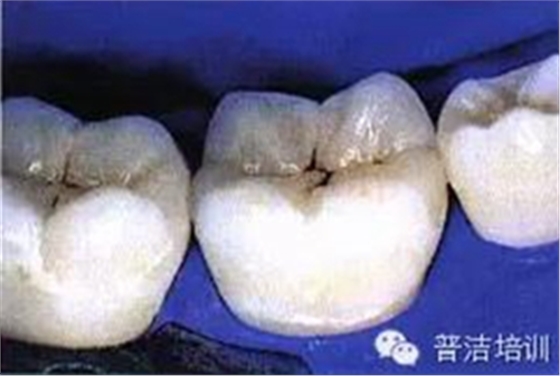

一、下頜后牙牙合面廣泛齲壞,檢查后決定行樹脂嵌體修復(fù)

十六、最終的修復(fù)體,是不是很漂亮

修復(fù)后一周復(fù)查